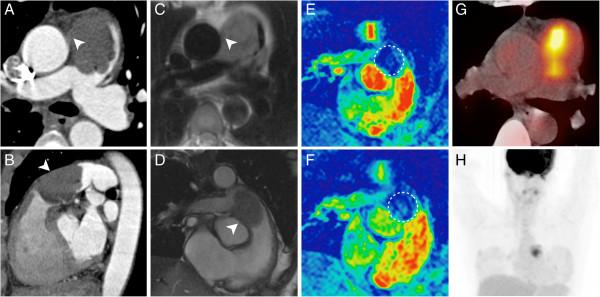

The median interval between the first imaging study and the final diagnosis was 11 weeks (0-12 weeks). The most frequently observed imaging findings suggestive of malignant disease in patients with sarcomas of the pulmonary arteries were a large filling defect with vascular distension, unilaterality and a lack of improvement despite effective anticoagulation. In patients with aortic sarcomas we most frequently observed a pedunculated appearance and an atypical location of the filling defect. The F-18 FDG PET(/CT) examinations demonstrated an unequivocal hypermetabolism of the lesion in all cases (4/4). MRI proved lesion vascularization in 5/6 cases.

首次影像检查与最终诊断的中位间隔时间为11周(0 - 12周)。肺动脉肉瘤患者中最常观察到的提示恶性疾病的影像表现为伴有血管扩张的大充盈缺损、单侧性以及尽管进行了有效的抗凝治疗但仍无改善。在主动脉肉瘤患者中,我们最常观察到带蒂外观和充盈缺损的非典型位置。F-18 FDG PET(/CT)检查在所有病例(4/4)中均显示病变明确的高代谢。MRI在5/6例病例中证实了病变的血管化。